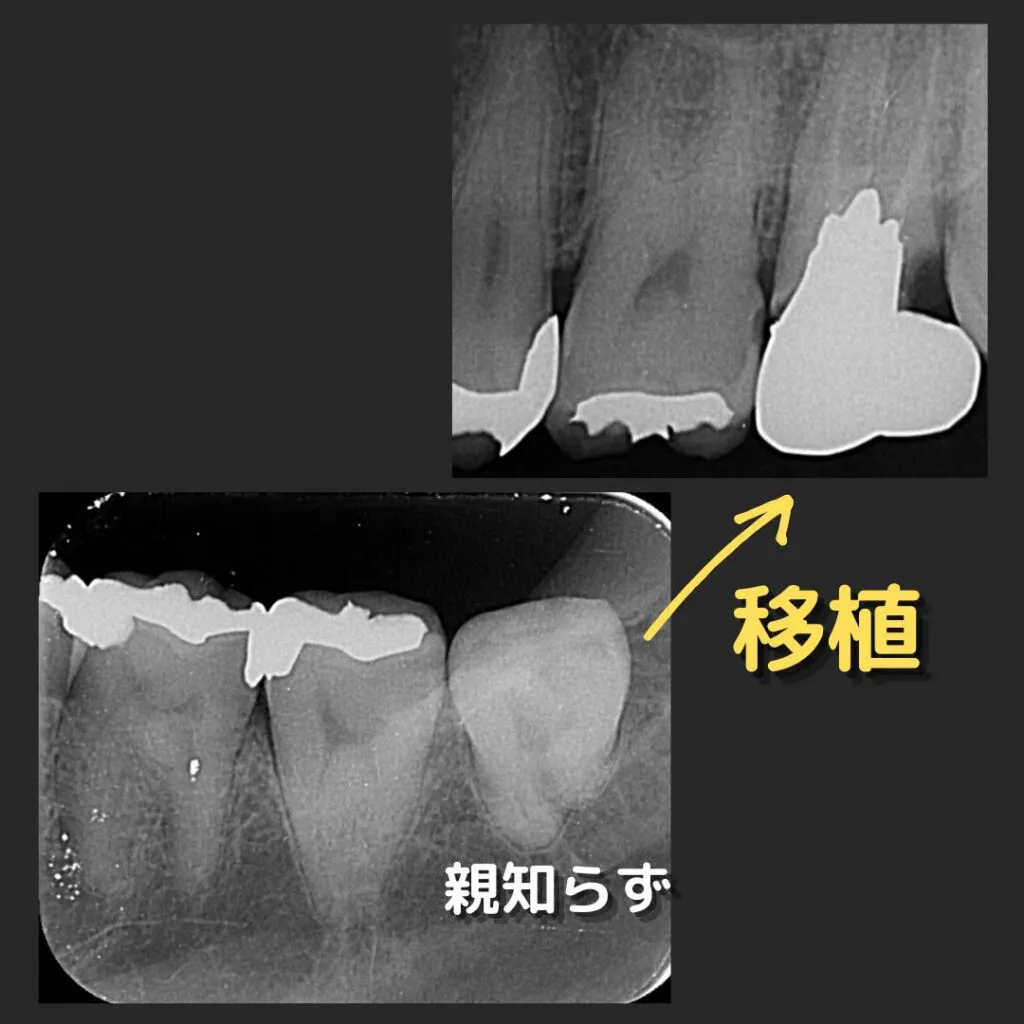

症例1(虫歯が大きく残せないため、親知らずを移植しました)

| 治療のリスクについて | タバコは傷の治りを悪くします。 出来るだけ禁煙していただくか、本数を減らしていただけるようお願いします。 静脈が多い所を切るので、内出血や腫れることがあります。 術後すぐは、歯が少し揺れます。 |

|---|---|

| 費用 | 移植手術…………………………………………………66,000円 顕微鏡を使用しての神経処置…………………………66,000円 被せ物(ジルコニア)………………………………126,500円 合計……………………………………………………258,500円 |

※すべて税込